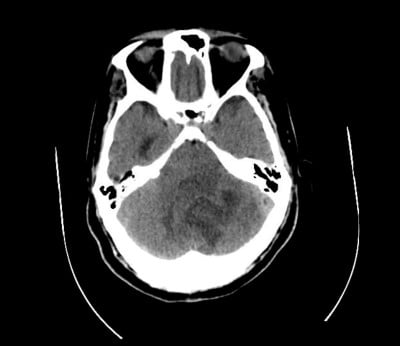

The patient had been discharged 5 days earlier from a brief admission after being diagnosed with anemia and liver lesions that did not demonstrate neoplastic process on biopsy. A CT scan of the head at this encounter revealed a large, left-sided cerebellar mass with edema resulting in displacement of the fourth ventricle and hydrocephalus. Mannitol and dexamethasone were given in the ED, and neurosurgery was consulted. The patient’s mental status continued to deteriorate and he was intubated, allowing neurosurgery to place an EVD. The patient was admitted to the neuro ICU with initial considerations favoring subacute stroke vs. mass.

Image 1: Hospital day 1